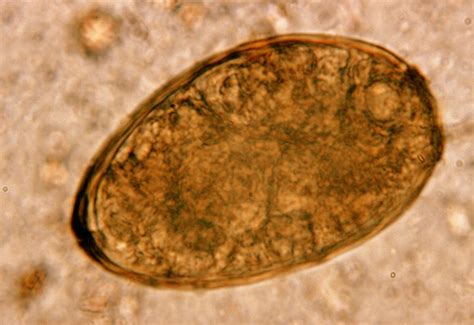

Zoonosis Salmonella

Salmonella Bacterium

Salmonella in Animals

Zoonosis

Salmonellosis

Salmonella Transmission in Animals